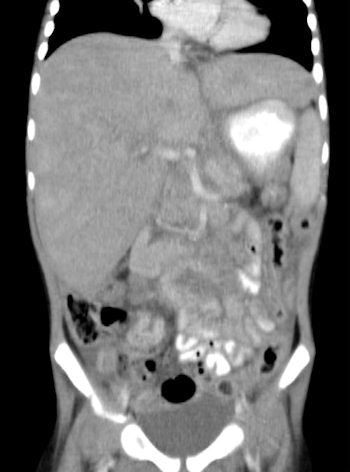

![Chest CT of 8-day-old girl with respiratory distress (80 kV, 51 average effective mAs, CTDIvol = 2.3 mGy, DLP [dose length product] = 33 mGy cm, E[effective dose] = 1.1 mSv. CT was performed to exclude congenital lung abnormalities because of family history and small volume lungs. Image shows ground glass opacity and septal lines consistent with respiratory distress syndrome. In all four figures, CTDIvol and DLP are expressed in terms of the 16 cm CT dosimetry phantom; these should be divided by approximately two to be expressed in terms of the 32 cm CT dosimetry phantom. Effective dose was calculated from DLP using conversion coefficients specific to this scanner and using the International Commission on Radiological Protection Publication 103 definition of effective dose. All images courtesy of Zoe Brady, PhD.](https://img.auntminnieeurope.com/files/base/smg/all/image/2012/08/ame.2012_08_15_08_57_30_715_2012_08_15_pediatrict_CT_pic1.png?auto=format%2Ccompress&fit=max&q=70&w=400)

The researchers compared average dose values at the Royal Children's Hospital (RCH) in Melbourne with international DRLs for common pediatric CT examinations. They found the use of 80 kV for both chest and abdomen/pelvis imaging in children younger than 5 years old leads to a significant dose saving, but conceded there is potential for dose optimization by reducing scan lengths for body examinations for children older than 5 years old. The plan now is to review these protocols to determine whether there is appropriate justification for the extended scan lengths.

The authors carried out a retrospective audit of patient records for pediatric CT brain, chest, and abdomen/pelvis exams. Demographic information, exam parameters, and dose indicators (volumetric CT dose index [CTDIvol] and dose-length product [DLP]) were collected for 220 patients: 100 for CT brain exams and 60 for each of the CT chest and abdomen/pelvis exams. Local DRLs (LDRLs) were derived from mean survey values and the effective dose was estimated from DLP values. The normalized CTDIvol values, mAs values, and scan length were assessed to better identify parameters that could be optimized.

The LDRLs across all age categories were 18-45 mGy (CTDIvol) and 250-700 mGy cm (DLP) for brain examinations; 3-23 mGy (CTDIvol) and 100-800 mGy cm (DLP) for chest examinations; and 4-15 mGy (CTDIvol) and 150-750 mGy cm (DLP) for abdomen/pelvis examinations. Effective dose estimates were 1.0-1.6 mSv, 1.8-13.0 mSv and 2.5-10.0 mSv for brain, chest, and abdomen/pelvis examinations, respectively. The RCH mean CTDIvol and DLP values were similar to or lower than international DRLs.